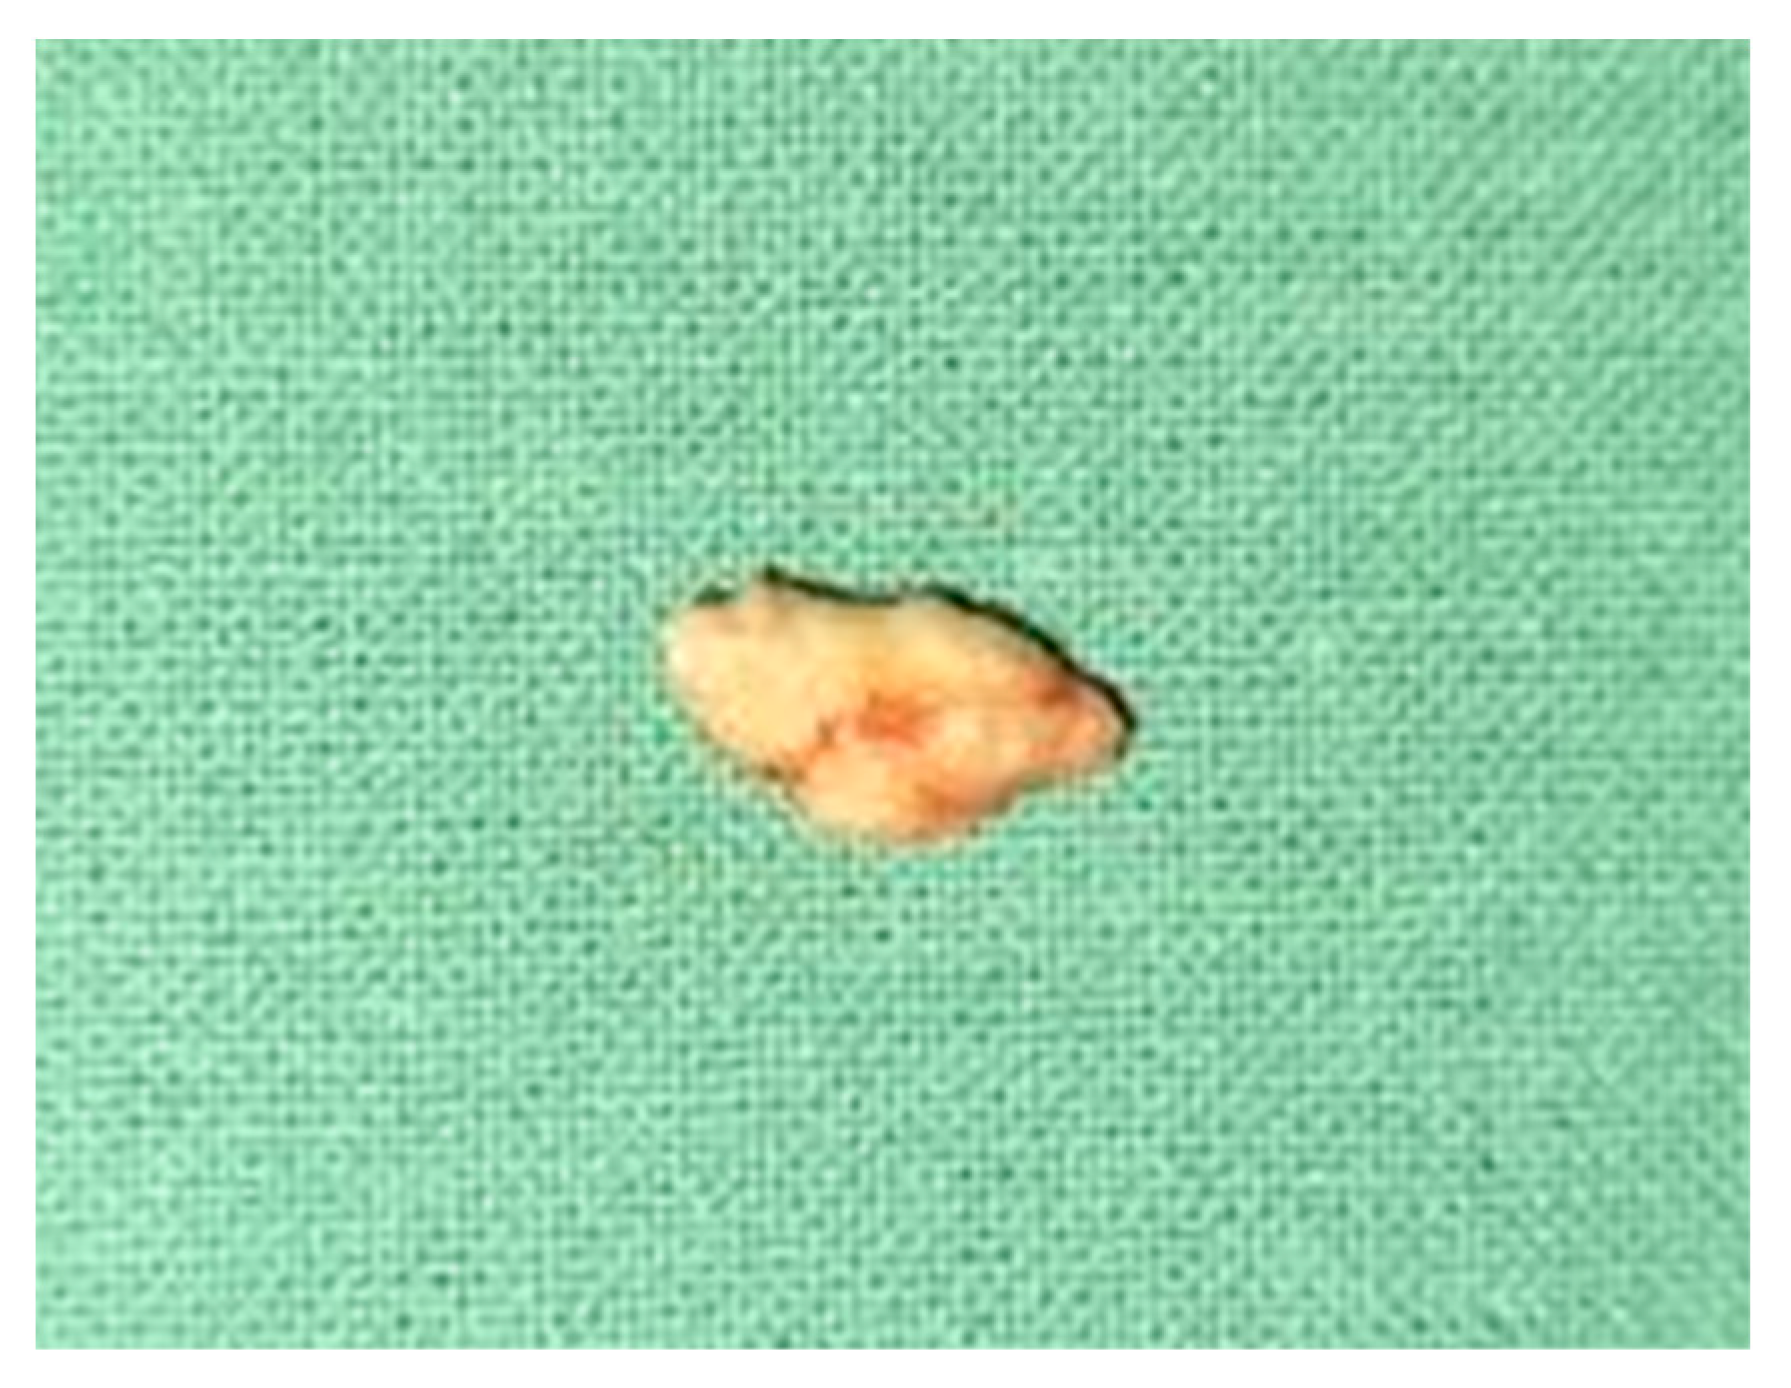

2. Case Report